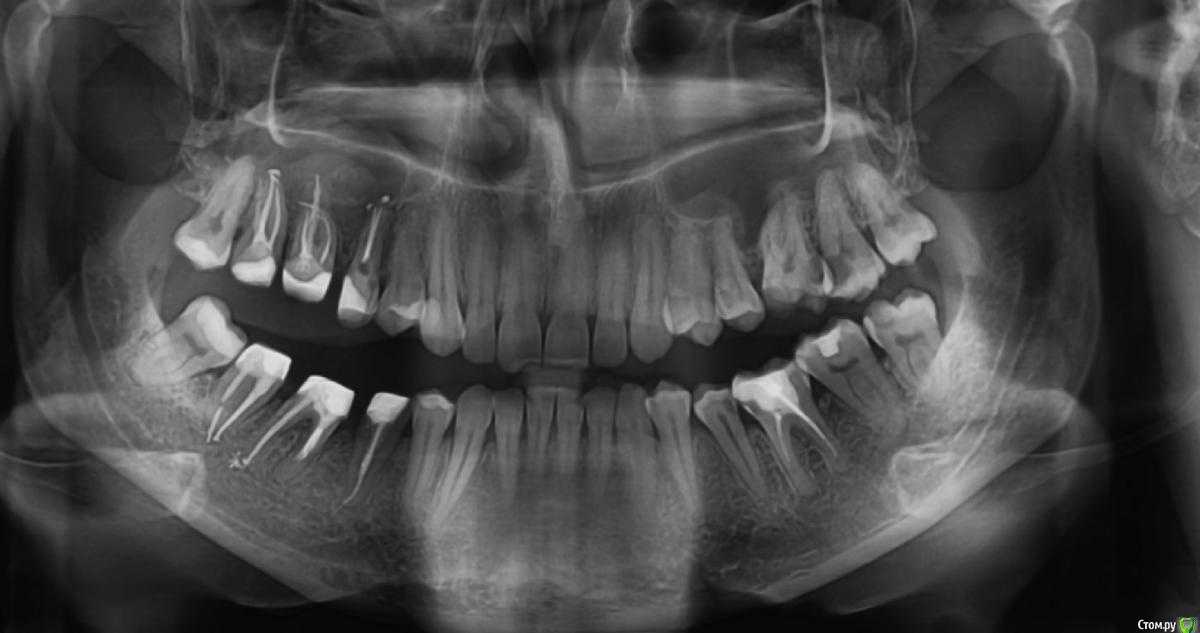

vicTORYa Опубликовано 24 мая, 2016 Поделиться Опубликовано 24 мая, 2016 Здравствуйте.В сентябре 2015 года лечила зубы с правой стороны.Снимок до леченияЛечили нижние 4,5,6,7,8 и верхние 3,4,5,6,7,8 зубы справа. В 5 и 7 верхних зубах случилась перфорация пазухи, врач поставил ультракал на месяц. Остальные зубы запломбировал постоянными пломбами, в каналы гуттаперчю поставил.В октябре пришла долечить 5 и 7 зубы. 5 запломбировали, а в 7 обнаружилась перфорация корня, врач запломбировал этот перфорированный канал какой-то специальной пастой (названия не помню). Два верхних и три нижних подготовил под коронки. Коронки решили ставить позже.Всё ждала, когда боль пройдет, но в некоторых зубах она так и не прошла, на тот момент при нажатии на зубы или постукивание болели 5, 6, 7 верхние (кажется 8 тоже), нижний 7 и немного ныл 5 нижний. Сделала панорамный снимок и пошла к врачу, он направил к ЛОРу так как увидел пятно в пазухе.Снимок на тот моментЛОР послал на КТ пазух.Сказал, что это кистозно-полипозное образование и его нужно удалять.Так ничего и не делала, оставила ситуацию в подвешенном состояние так как я в полной растерянности.На данный момент болят при постукивание верхние 5,6,7, 8 но совсем немного, при нажатие 6,7. Нижний 7 болит при нажатий и постукивание, немного 5 (и как будто ноющая боль бывает).Свежий снимок.Помогите пожалуйста разобраться. Что с этими зубами? Почему они продолжают болеть? Насколько большая проблема материал, выступивший за предел корня? Нет ли вокруг него воспалительного процесса? И что мне с ними делать дальше? Одевать ли коронки? Или может какие-то из них вообще подлежат удалению? Что с пазухой? Если нужны какие-то другие срезы из КТ могу выложить. Заранее спасибо. Ссылка на комментарий

Паращук Роман Опубликовано 24 мая, 2016 Поделиться Опубликовано 24 мая, 2016 В верхних зубах материал за пределами корня и скорее всего в пазухе. Может стать причиной воспалительных процессов или усугубить их,или поддерживать. В нижней 7ке выведенная гуттаперча за пределы канала. Если есть проблемы,то их нужно решать или организм решит их за вас. В верхних зубах эндоскопически через носовой ход,в нижнем попробовать через каналы,если нет хирургически. Ссылка на комментарий

vicTORYa Опубликовано 13 июня, 2016 Автор Поделиться Опубликовано 13 июня, 2016 Спасибо за ответ. Прояснили мне ситуацию. Немного начинаю понимать, что делать.То, что проблемы нужно решать я понимаю, не понимала как. Стоматолог (на то что они болят уже на протяжение более полугода и значит там что-то не так) посмотрел снимок, постучал по зубам сказал, что все в порядке с зубами, нужно ставить коронки, а вот пятно в пазухе не хорошо и надо сходить к лору. Лор сказал, что надо удалять эту кисту, которая там образовалась. Но ничего не сказал про пломбировочный материал. Поэтому я ничего так и не сделала до сих пор со всем этим, так как не совсем понимала зачем удалять кисту если не решать проблемы с зубами, ведь она там может опять появится, и вот оказывается еще и другие проблемы давать. И как ставить коронки если зубы болят.С другой стороны, боль в зубах постепенно снижается, зимой болели сильней, на данный момент немного болит 6,7 верхние и 7 нижний при постукивании или нажатие. И еще немного 5 нижний, но там другая боль какая-то, немного болит десна при надавливании на неё, а сам зуб болит как будто на нем долго жевали, в общем даже не знаю, как описать)Если подытожить, правильно ли я поняла? Зубы эти удалять не нужно, а нужно решать проблемы с материалом пломбировочным, и потом можно ставить коронки? И ещё вопрос, можно ли подождать ещё пару месяцев и если боль совсем пройдёт, то ставить коронки и нижние не перелечивать, а верхние удалять эндоскопически через нос? Ссылка на комментарий